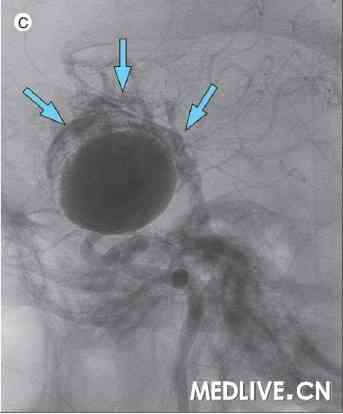

为明确该动脉瘤的解剖学特征,进行螺旋扫描以重建三维影像。在进行螺旋扫描时,动脉瘤在之前的破裂点顶部再次破裂,出血迅速渗入蛛网膜下腔和脑室(附图C,见网络视频)。 随后对颈内动脉采用弹簧圈和可分离式球囊进行血管内栓塞。次日,患者被确认脑死亡,撤除医疗支持。

C图:螺旋扫描图像显示,出血进入蛛网膜下腔